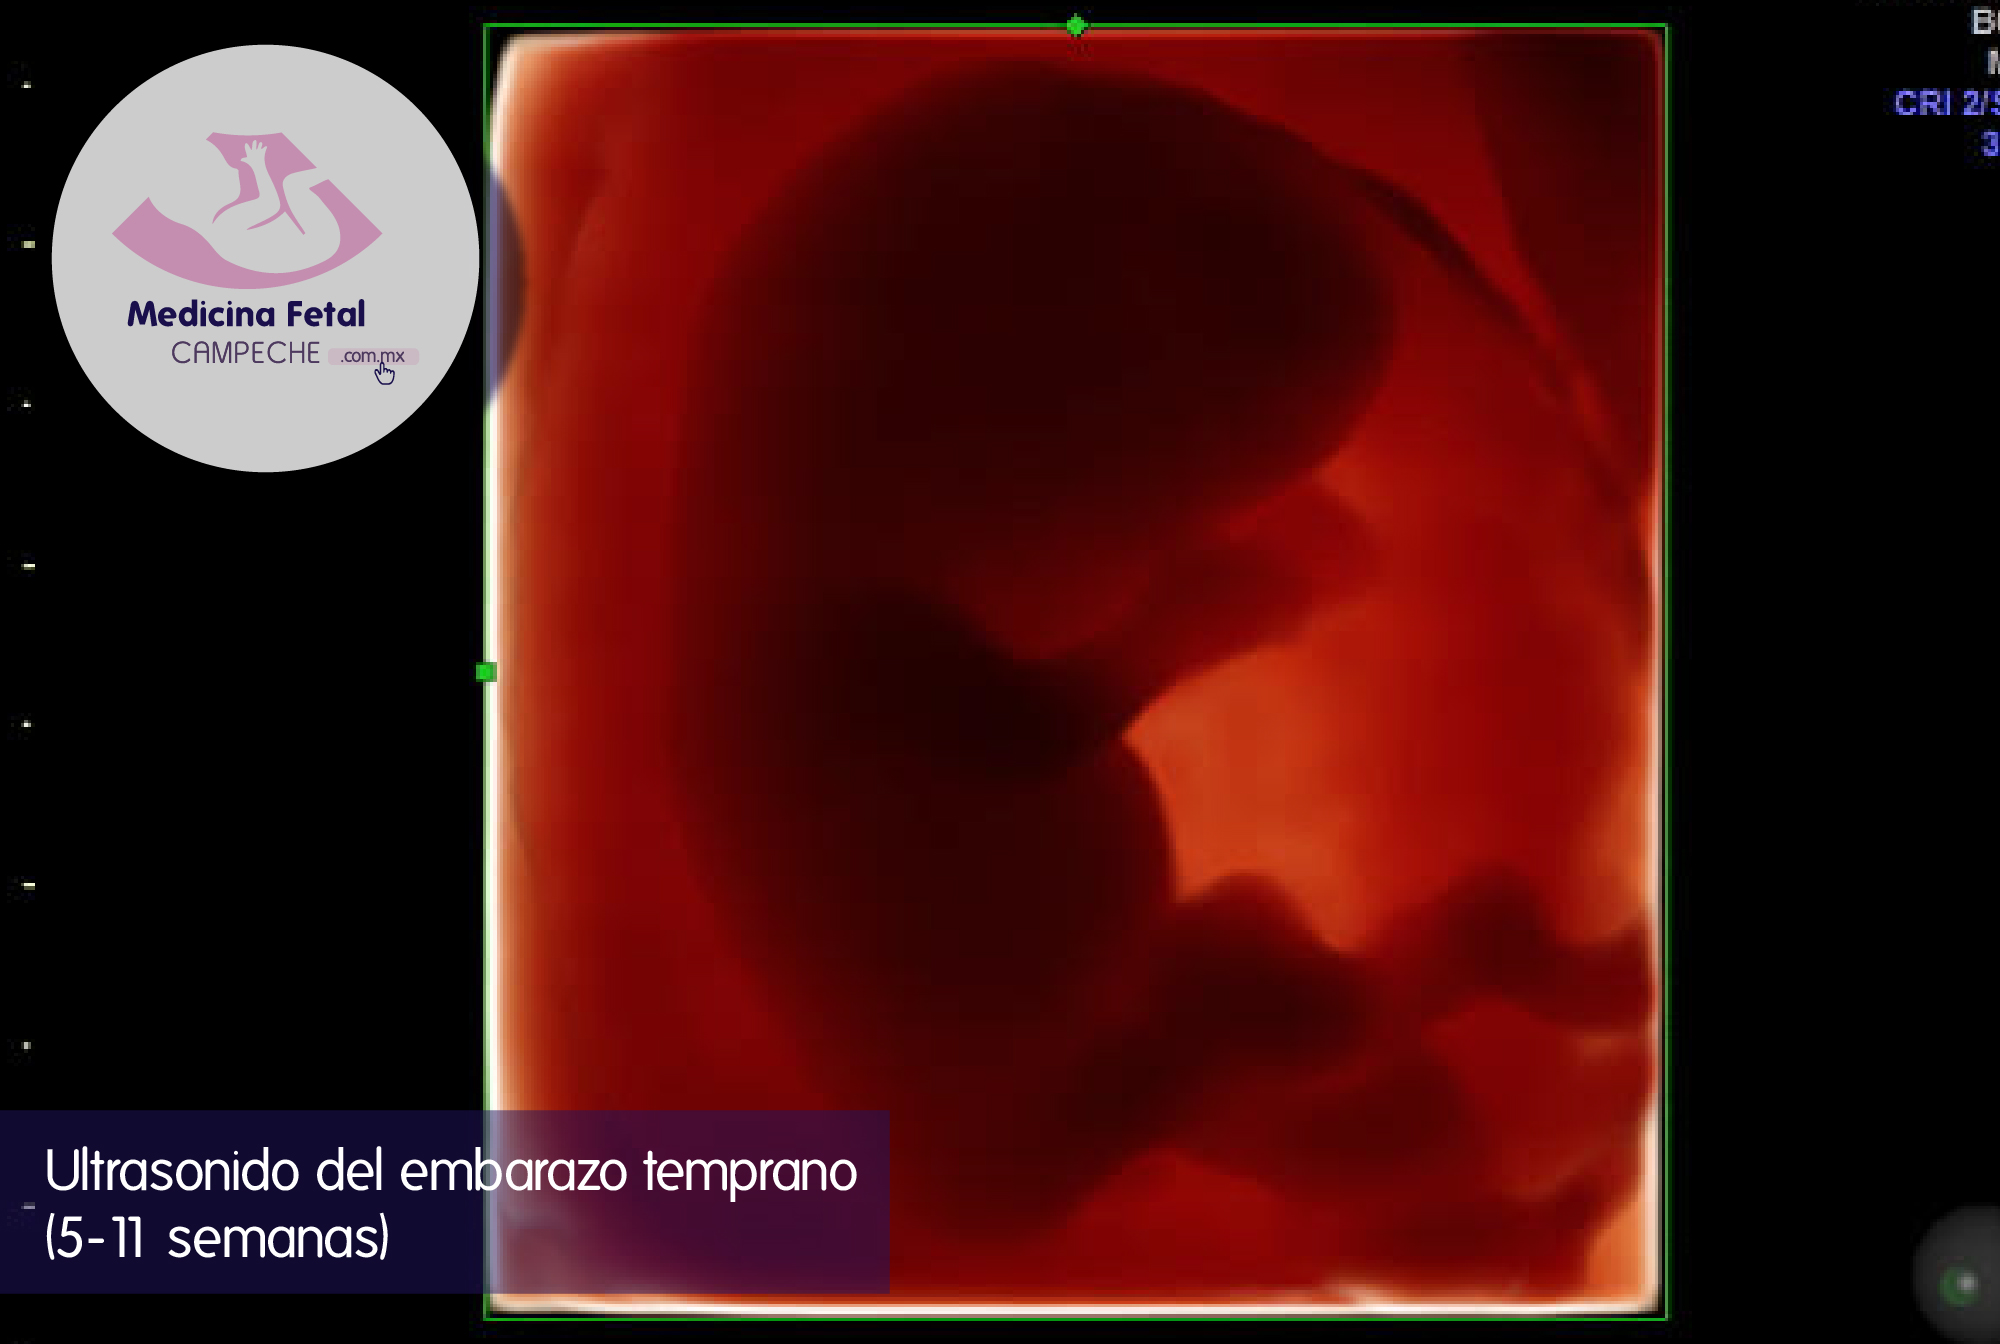

Confirmar la presencia de tu embarazo.

Que la localización de éste se encuentre dentro del útero en el lugar correcto o, en caso contrario su presencia fuera del útero o matriz.

A partir de que se identifica el embrión determinar si tu embarazo es de un solo bebé o más de uno, ya que cambian el pronóstico y la manera de vigilancia de éste.

Confirmar la presencia del embrión y del latido cardíaco.

Importante también es que nos permite evaluar las estructuras pélvicas maternas y podemos determinar si existe presencia de alguna tumoración como fibromas o tumores de ovario que puedan influir en el desarrollo de tu embarazo o al momento del nacimiento.